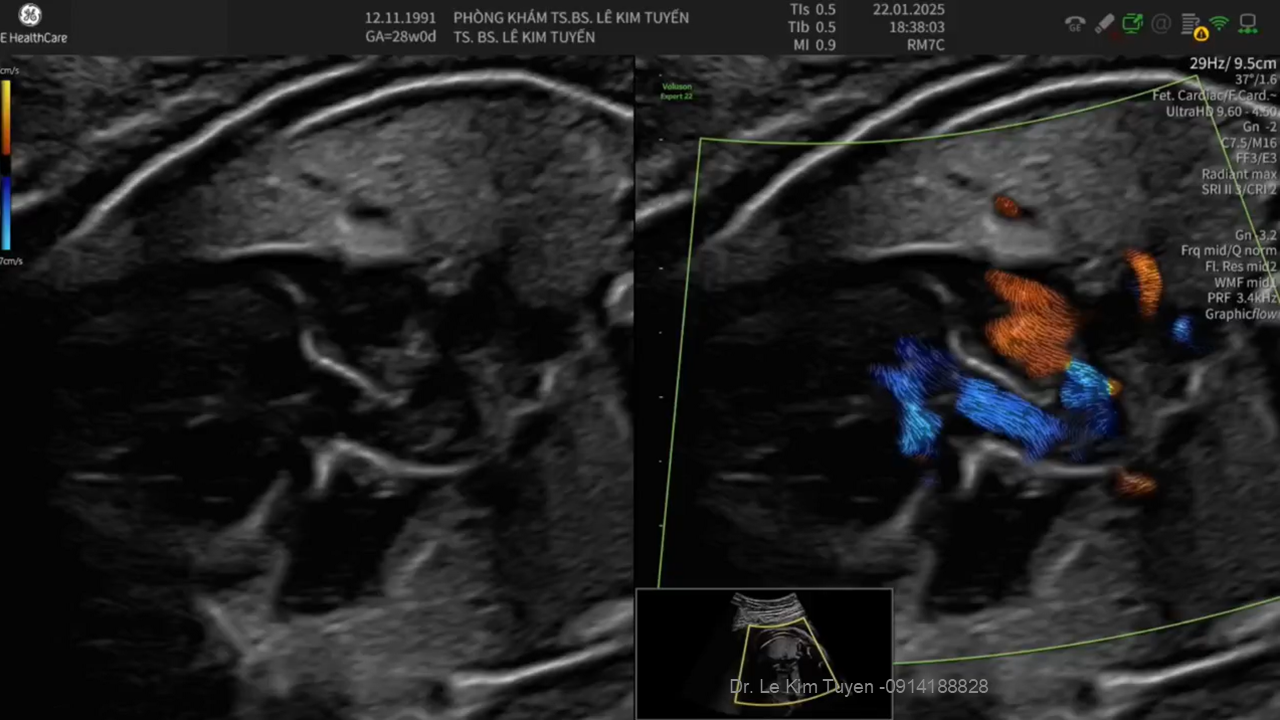

Áp dụng công nghệ Graphicflow trong phát hiện bệnh tim bẩm sinh cần cấp cứu sơ sinh

TS. BS. Lê Kim Tuyến

Bệnh viện Tim Tâm Đức